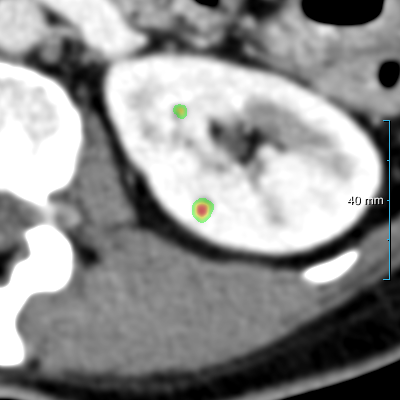

(c) Contours

Refer to caption

Figure 7: Comparison of three cases on the test set B30 between experiment 1  , the reference standard, and the second observer. (a) shows the original slice. (b) shows the heatmaps (predictions prior to post-processing, using a color table mapping [0,1] from transparent to green to red) of experiment 1  . (c) shows the final predictions (red contours) of experiment 1  , the reference standard (green contours), and the second human observer (yellow contours). The window center and window width used for all slices were 60 HU and 360 HU.

Segmenting kidney abnormalities is challenging due to the similarity between tumors in the collecting system and kidney cysts. For instance, Figure 7 shows three cases from dataset B30 where our method returned some false positives due to the similarity with tumors in the collecting system. Each case shows the kidney abnormality predictions of experiment 1   prior to post-processing in the second row as heatmaps. While the third row shows the post-processed segmentation, reference standard, and second observer as red, green, and yellow contours, respectively. In all three cases, a false positive by our method is present, indicated by an isolated red contour. In case 1, the false positives are abnormalities in the collecting system, which have a similar image intensity as the cysts, similarly, the second observer also segmented one of these abnormalities in the middle region. In case 2, the false positive appears as a small cyst-like region, while in case 3, it resembles an irregular region in the kidney. Figure 9 shows a comparison of the final prediction in annotation format 1 of experiment 1  , the reference standard, and the second observer represented as red, green, and yellow contours, respectively. This figure shows the best and median cases of datasets B20 and B30 and the Dice score of each case computed between experiment 1   and the reference standard.